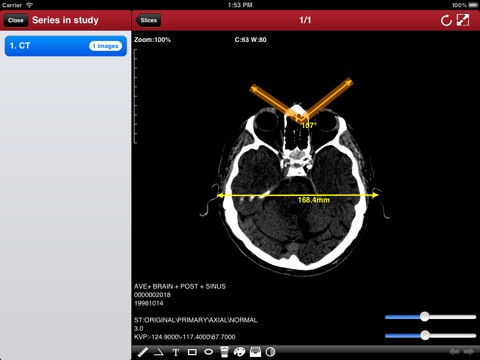

"DicomBox" is a DICOM software for iOS: DICOM is the digital standard for storing and transferring medical images. DicomBox allows downloading and manipulating series of images directly on your iOS device. DicomBox is capable of displaying images from all imaging modalities in their native standard DICOM format used by the medical/scientific industry. DicomBox is a fully DICOM-compliant listener that can receive images from any DICOM imaging device through WiFi/3G networks.